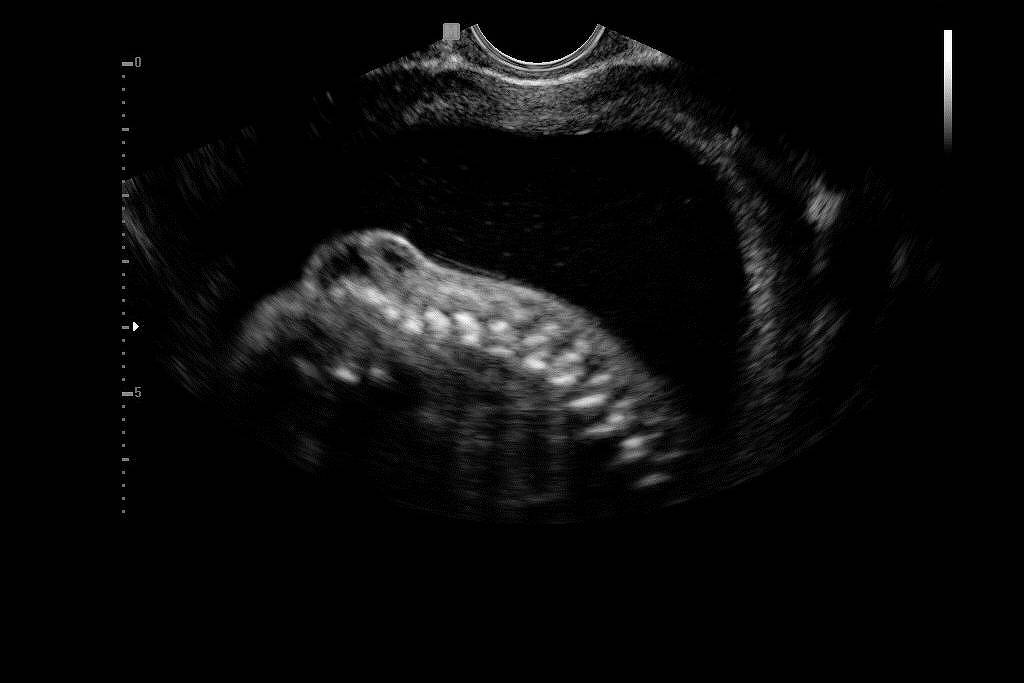

O exame de ultrassom morfológico já estava terminando quando o bebê Enzo, ainda na barriga de Karem Simões, 31, resolveu virar um pouquinho de lado. Foi o suficiente para acender a luz amarela: o calombo no finzinho da coluna não era normal.

A gestação estava na 20ª semana, quando já é possível identificar malformações.